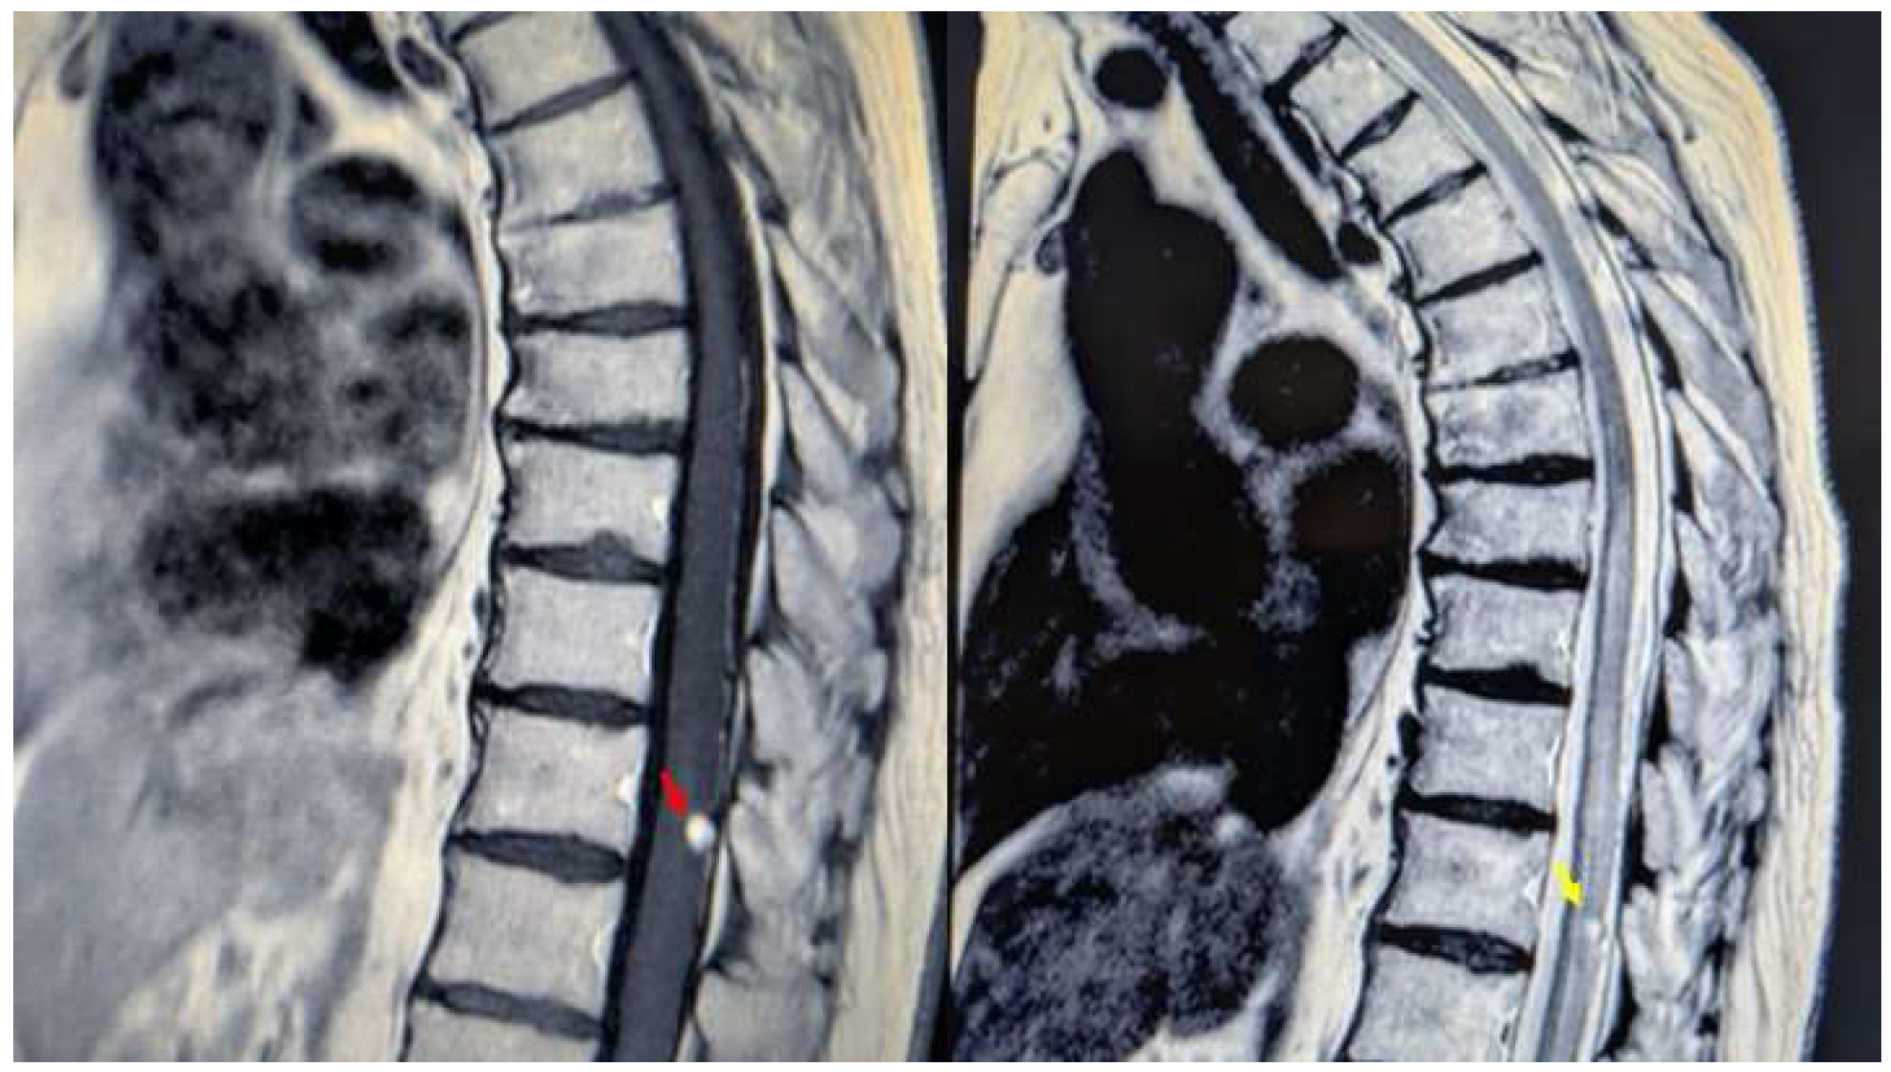

A 76-year-old woman presented with a six-month history of progressive dorsolumbar pain. Neurological examination revealed significant pain but preserved lower limb strength; bladder dysfunction was present and worsening overtime. Magnetic resonance imaging (MRI) of the thoracic spine revealed an expansive lesion at the D11 vertebral level [Figure 1]. Neurosurgical evaluation indicated the need for surgical resection. The patient’s medical history included long QT syndrome, osteoporosis, and bilateral carpal tunnel syndrome.

Figure 1. MRI of the thoracic spine. Left: T1-weighted image showing the expansive lesion at the D11 level (red arrow). Right: T2-weighted image revealing the lesion with surrounding edema (yellow arrow). .